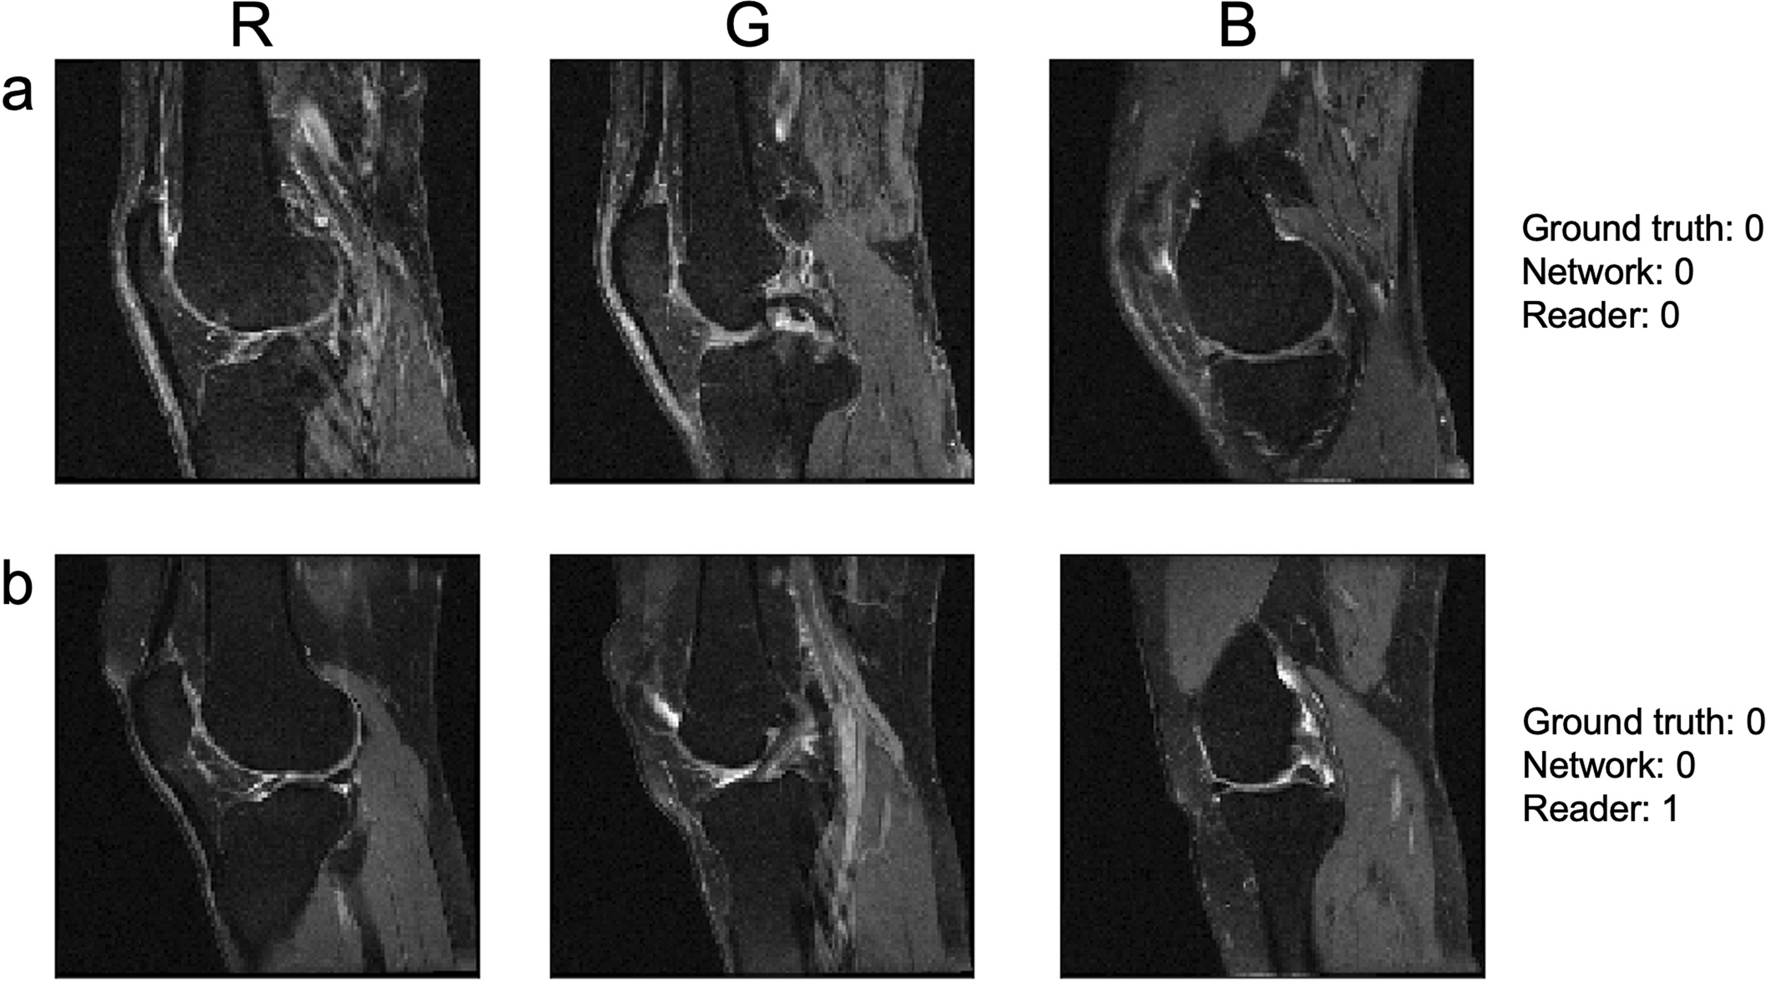

Figure 6

From: Automatic estimation of knee effusion from limited MRI data

Two sample subjects, one with agreement between the dNN and the reader and the other with disagreement. As described in Fig. 2, the three slices were combined into a color image as shown in the top labels to facilitate classification by 2D image-based networks. (a) A subject where the dNN and reader assessments agreed with the OAI class (both giving a value of 0). (b) A subject where the dNN agreed with the ground truth of normal fluid amounts, while the reader estimated effusion.